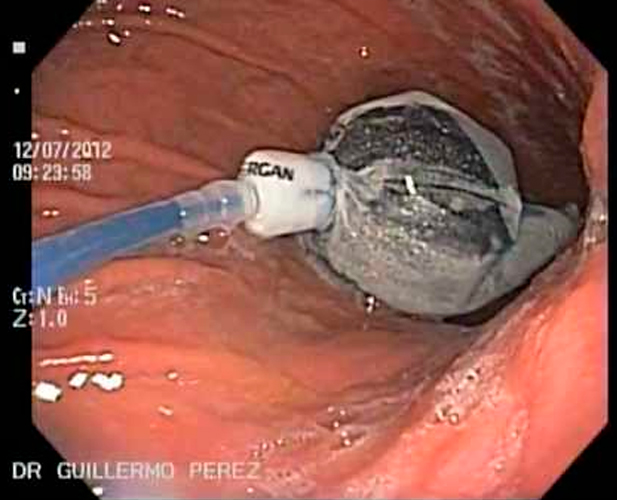

BALÓN GÁSTRICO

Es una de las soluciones a sus problemas de sobrepeso y obesidad mórbida, con este nuevo método se Índice de masa corporal (IMC) perderá de 5 a 6 puntos (de 10 a 30 kg) en 6 meses, dependiendo de los hábitos alimenticios que adopte.

Esta novedosa técnica es ambulatoria y no quirúrgica que se practica con sedación profunda